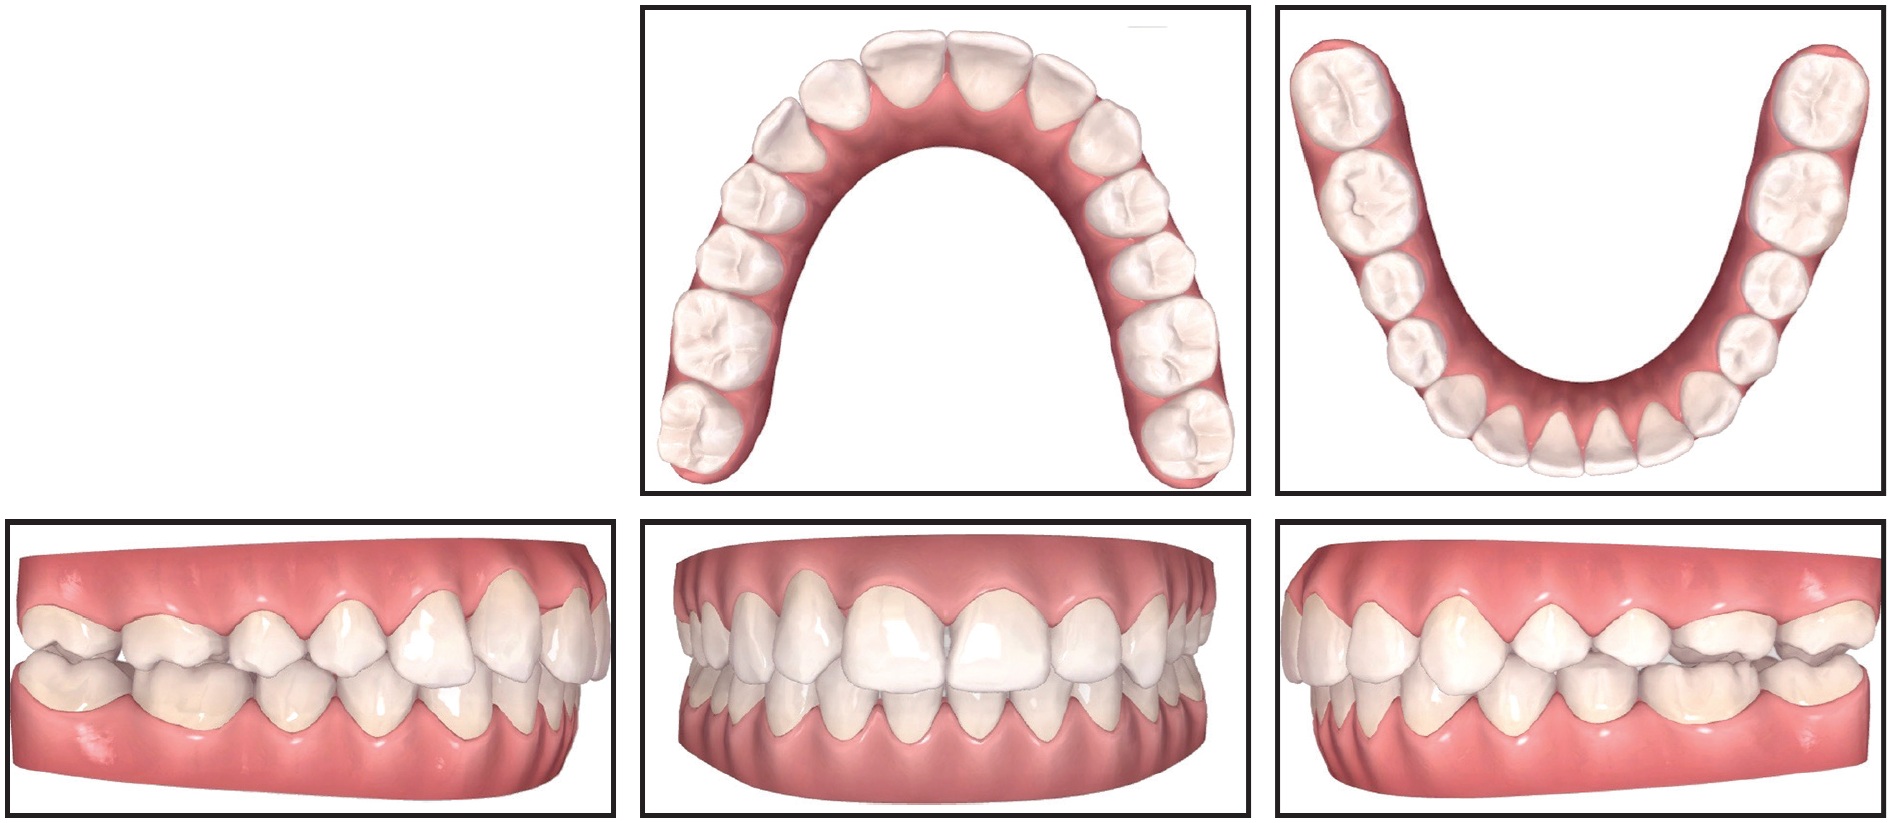

Treatment objectives were to resolve the malocclusion and move the ectopic canine into the dental arch. As the least invasive option, the treatment plan would begin with extraction of the deciduous canine and the two supernumeraries, followed by correction of the bilateral Class II relationship, overjet, and overbite; recovery of the upper right canine; and final harmonization of facial esthetics. The patient and her parents preferred the use of Invisalign* clear aligners because of her history of allergic reaction to metals. Considering the current capabilities of aligner treatment, we believed it would be biomechanically effective for correction of the transposition. Based on the ClinCheck* simulation, the treatment would last about 24 months, including two series of refinement aligners (Fig. 3).

Fig. 3 ClinCheck* treatment plan.